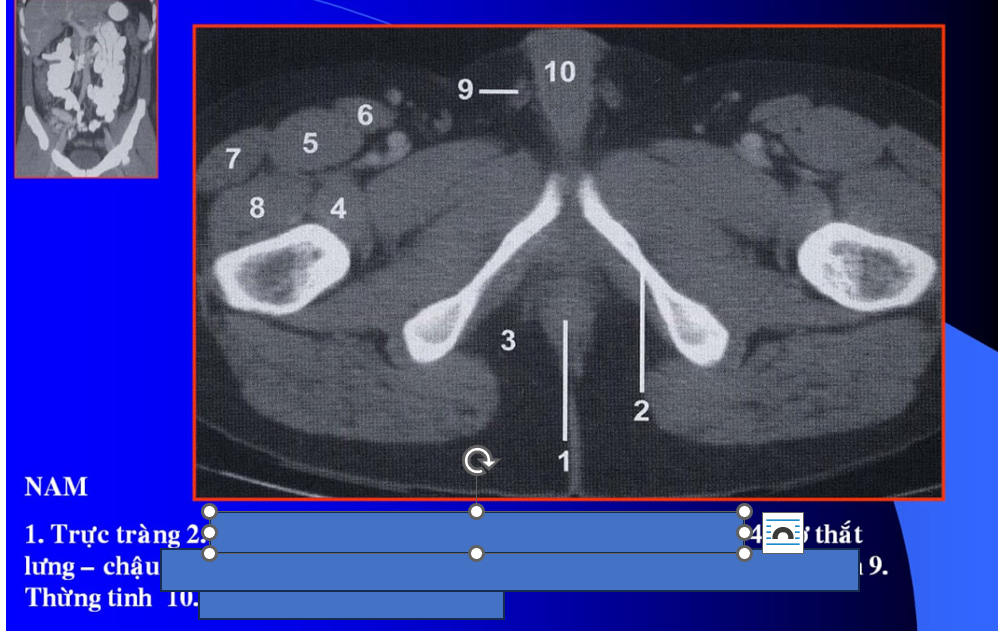

cq trong hình ?

cơ tl? cơ chậu?

manh tràng? x cùng?